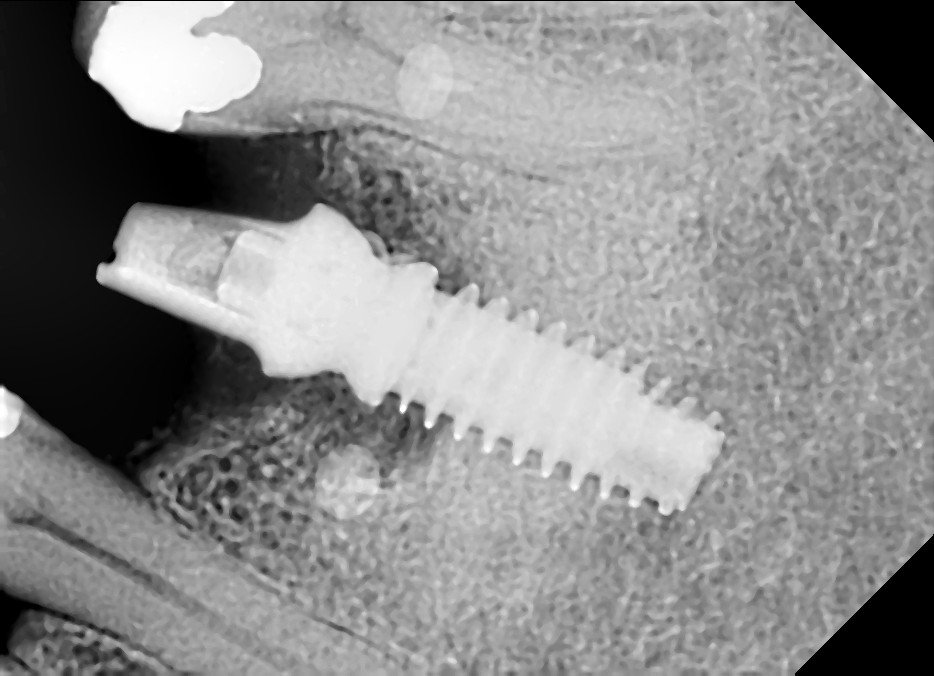

Buenas tardes, tenemos este implante en una pieza 36 y no sabemos que marca ni modelo es.

Buenos días. No consigo descubrir que implante es. A ver si podéis ayudarme. Muchas gracias!

Estos implantes fueron colocados en Madrid mas o menos por 1985. Quiero quitar la protesis y por mas que perforo no encuentro las chimeneas y me da miedo cargarme la [...]

Buenas tardes, me ayudais con el implante más mesial? Gracias